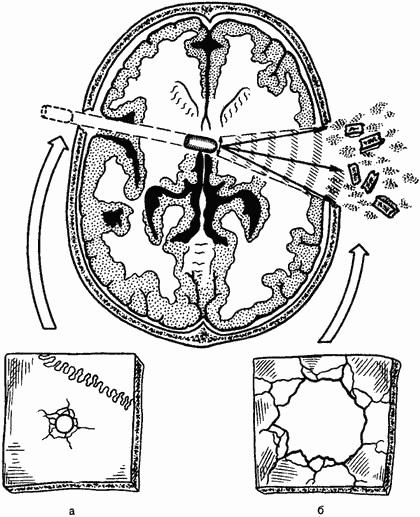

Bullet, károsítja az üreges test, amely egy folyadékot (. Gyomor-, húgyhólyag-, szív, stb), az említett ütközési energiát a folyadék - hidrodinamikus hatás jelentkezik. Ennek eredményeként, egy kis belépő egy üreges test felcsévélve azokból golyó kilépési terület van kialakítva nagy tépés (ábra. 70).

Ábra. 70. Az akció a lökéshullám élén lőtt koponya trauma. Típusú seb lyukak, és - bemenet; b - kimenet.

Damage lapos csontokban (koponya. Medence. Uszony, lapátok, szegycsont) megvannak a saját jellegzetességei. A külső lemez (kapcsolatban az irányt a golyók mozgás) lövedék kiütéssel kerekítve, többé vagy kevésbé megfelelő az átmérője a lövedék. A szemközti (belső) csontlemez sérült, hogy egy sokkal nagyobb területen. Kialakult egyfajta csonka kúp, a nagy bázisa, amely felé irányul a golyót. Azokban az esetekben, kárt házatlan golyó ponton bejegyzését a csontok puha marad fémrészecskék - ólom - sötétszürke perem széle körül a lyuk. Ez metallizáció jól kimutatható röntgen és laboratóriumi módszerek, és bizonyos esetekben még észrevehető szabad szemmel.